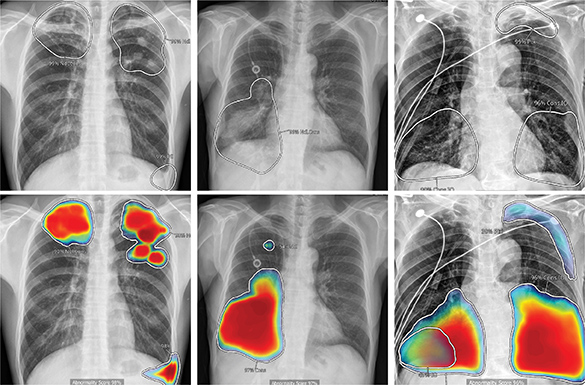

AI-Based Diagnostic Reference

RadTrainer includes AI-generated reference images that help trainees learn how AI-based analysis results are presented in clinical environments.